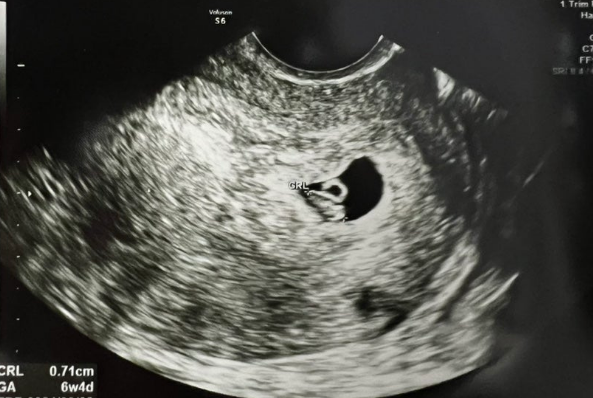

2024년 6월, 모델로 활동하던 20대 여성 양민희 씨는 손흥민 선수에게 자신이 임신했다며 태아의 초음파 사진을 전송했고, 이를 외부에 폭로하겠다며 거액을 요구했습니다. 손흥민은 당황했지만, 사생활 보호를 위해 3억 원을 건넨 것으로 알려졌습니다. 이후 양 씨는 “관련 사실을 더 이상 언급하지 않겠다”는 내용이 포함된 비밀유지 각서를 작성합니다. 하지만 사건은 여기서 끝나지 않았습니다. 2025년 3월, 양 씨의 새 남자친구인 40대 용 모 씨가 이 사실을 알고 손흥민 측에 다시 협박을 시도했습니다. 그는 “이 사건을 언론에 폭로하겠다”며 7천만 원을 추가로 요구했지만, 손흥민은 이번에는 강경 대응을 선택했고, 즉시 경찰에 고소장을 제출했습니다.

이번 사건에서 가장 큰 논란 중 하나는 “정말로 임신했는가?”였습니다. 경찰 조사 결과, 양 씨는 실제로 병원에서 임신중절 수술을 받은 기록이 확인되었으며, 그녀가 제출한 초음파 사진 역시 본인의 것으로 판명되었습니다. 하지만 그 임신이 손흥민 선수와 직접적인 관련이 있는지는 명확히 확인되지 않았습니다. 손흥민 측은 양 씨와 과거 연인 관계였던 점은 인정했으나, 양 씨가 주장하는 임신 시점과 손흥민의 입장은 명백히 다르며, 아이의 생물학적 부친이 손흥민이라는 근거는 없다는 입장을 고수하고 있습니다.